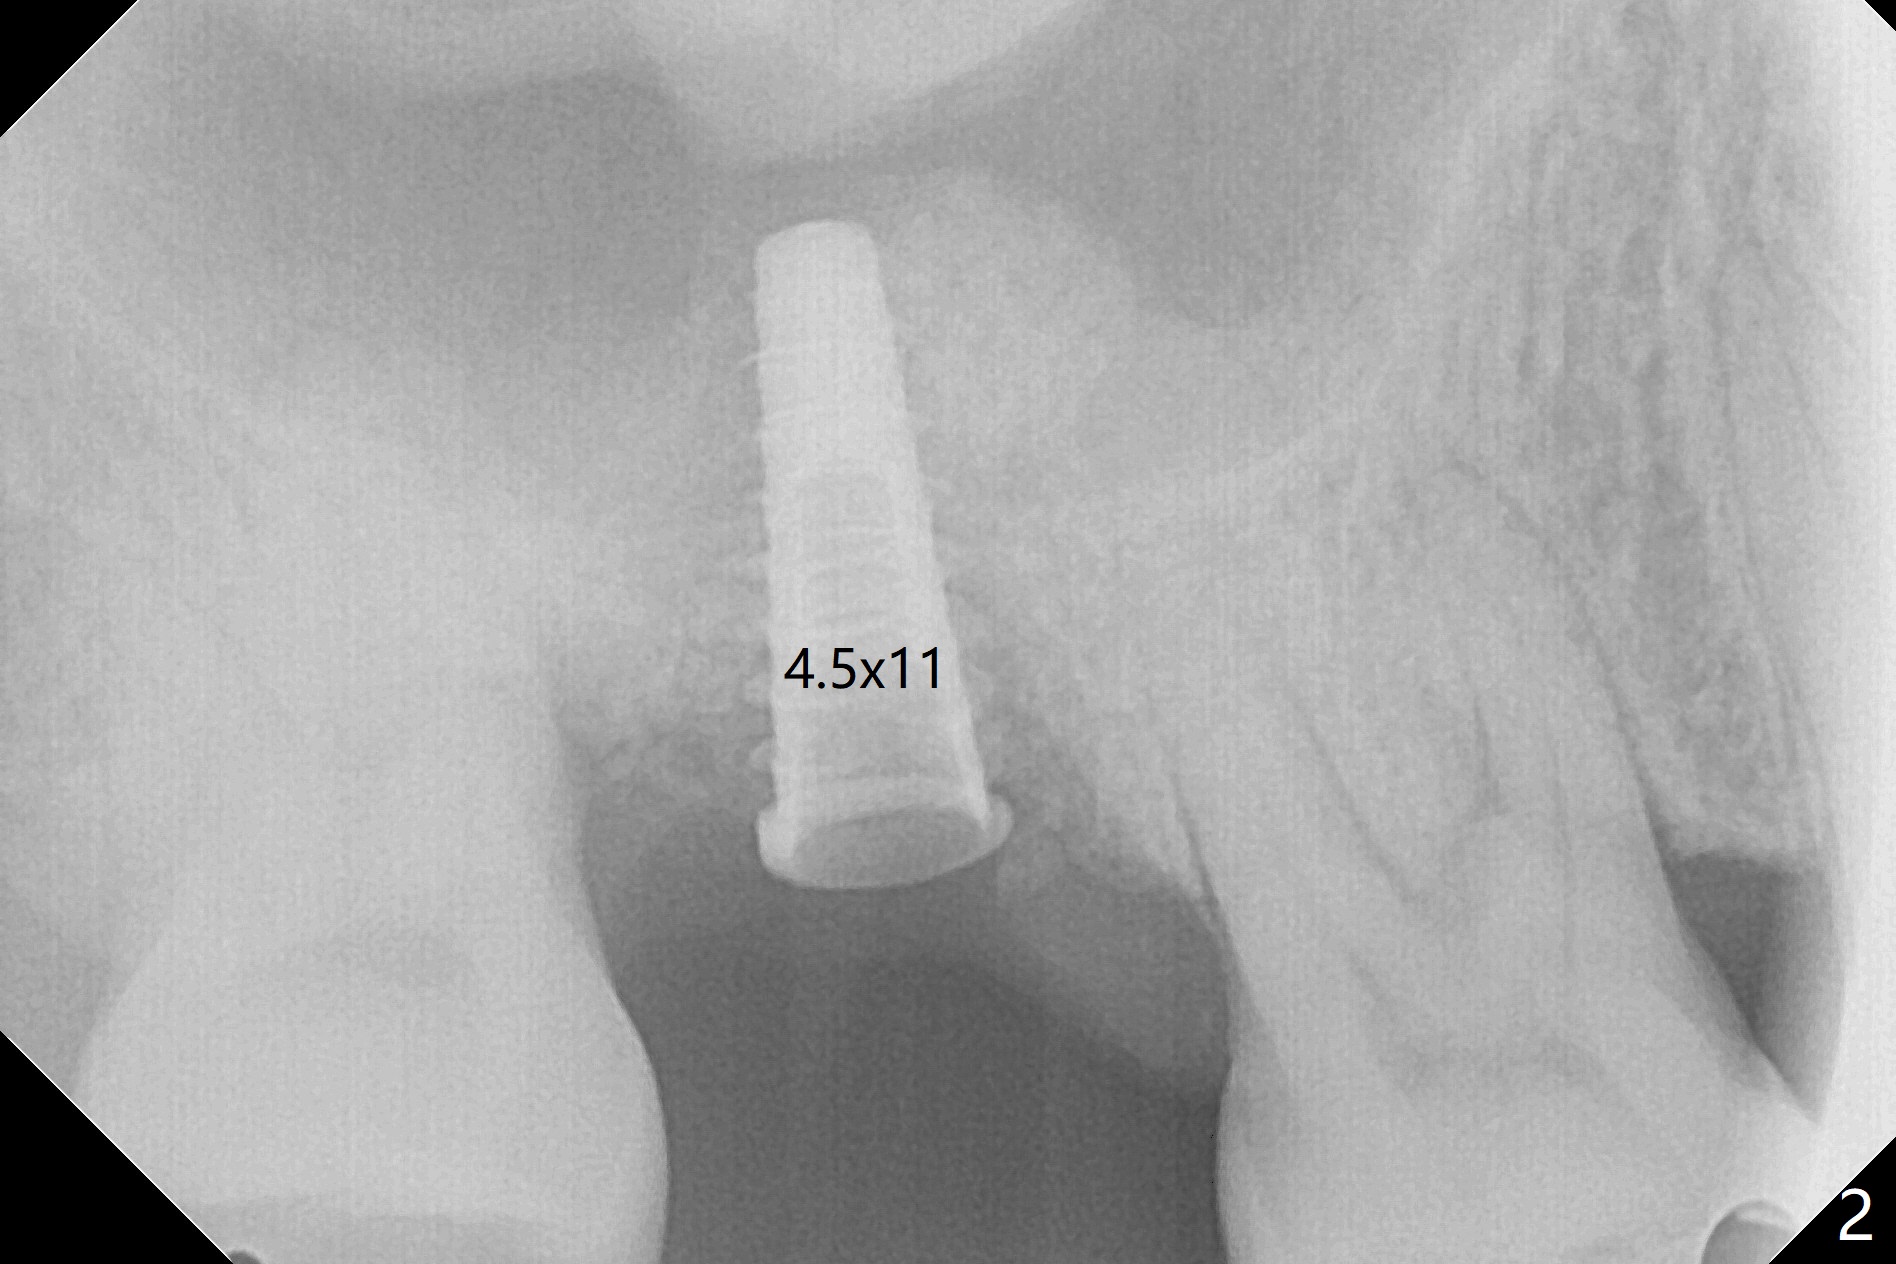

Not long postop, the patient called saying that #2 provisional had dislodged. Due to his busy schedule and coronavirus outbreak, he returns nearly 4 months postop. The abutment is distalized and loose with the underlying implant (5x9 mm). The latter is removed before local anesthesia (Fig.1 distal defect). After initial debridement, a 2.2x13 mm drill is used with a guide of 12 mm offset, followed by insertion of a 4.5x11 mm dummy implant with barely stability (Fig.2). A 5.5x9 mm is placed free hand initially, followed by guide with stability. But the implant has uncovered threads distolingual. Thorough debridement reveals that the sinus membrane has a small perforation. After placement of a piece of Osteogen plug, cortical chip and Vanilla hydrated with .25 cc of GEM21S is packed into the site with a condenser (Fig.3,4). The graft is fixed in place with Perio glue, followed by a piece of GEM Cap with the glue. Three to 4 months later, take CT for healing confirmation. Try to place a shorter implant (e.g., 5x7 mm) without getting into the sinus to reduce infection. In fact the Cap does not stay in place with loss of bone graft (8 days postop).